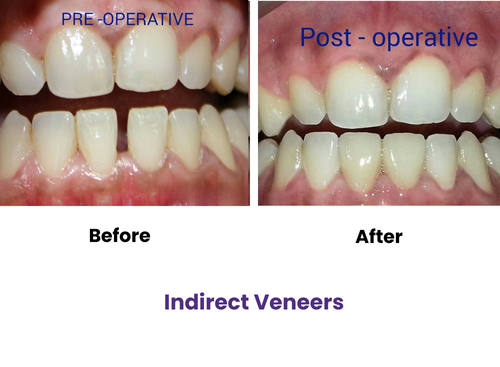

Direct veneers are applied in a single visit using composite resin for quick improvements.

Indirect veneers are custom-made porcelain shells that offer long-lasting smile transformations.

Both options improve shape, color, and alignment for a flawless finish tailored to your face.